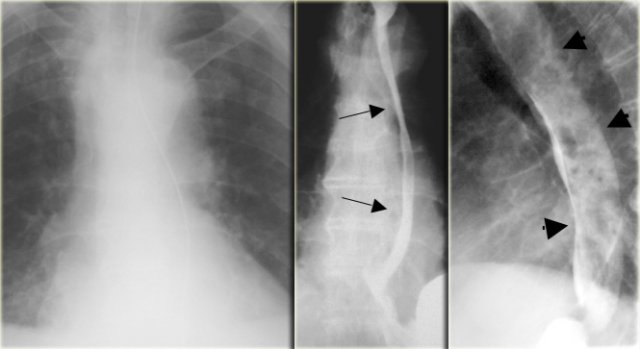

On the far left an intramural extravasation (arrow) after distal dilation for achalasia.

In the middle an intramural extravasation (arrow) after complicated endoscopy.

On the right a perforation after biopsy with extravasation of contrast material (arrow).

On the left downhill varices in a patient with a superior vena cava obstruction due to histoplasmosis.

On the barium study inconstant filling defects (arrows) represent downhill varices in upper esophagus.

The angiogram demonstrates collateral vessels including a dilated left superior intercostal vein (arrow).

The barium study demonstrates inconstant filling defects (blue arrows) due to downhill varices in upper esophagus.

CT demonstrates esophageal (red arrow) and mediastinal varices.